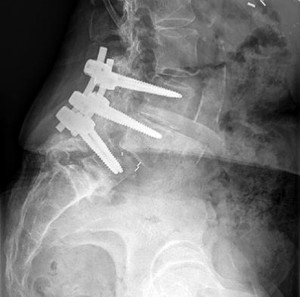

A 16-year-old elite male gymnast complains of chronic low back pain that is distinctly worse with spinal extension. He has failed 6 months of rest, physical therapy, and bracing.

Radiographs demonstrate a Grade II L5-S1 isthmic spondylolisthesis. He remains symptomatic. What is the most appropriate surgical intervention?

Explanation